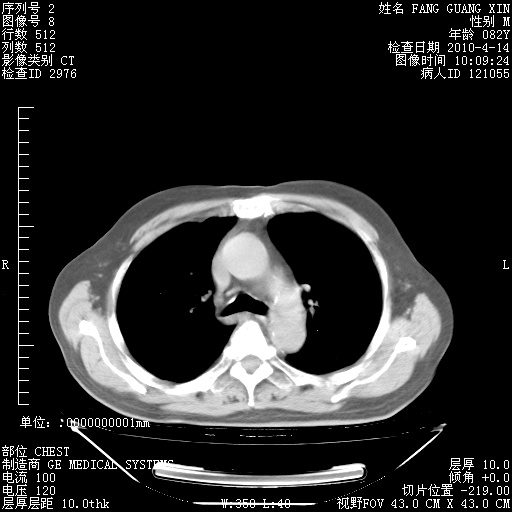

肺部CT平扫未见异常。